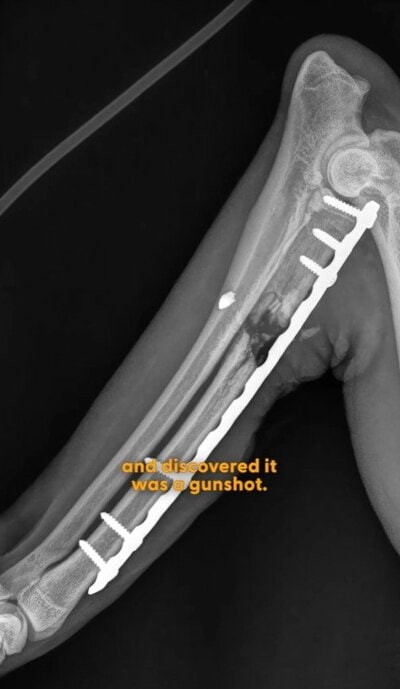

3. 【山で負傷した犬】なんと、負傷の原因は撃たれたことによるものだった

病院で負傷した足のレントゲンを撮ってみたところ、なんと撃たれた弾が。

コメント欄でも「弾? 誰が犬を撃ったんだ!!!」

そして、そして最終的には負傷した足を切断することになったのです。